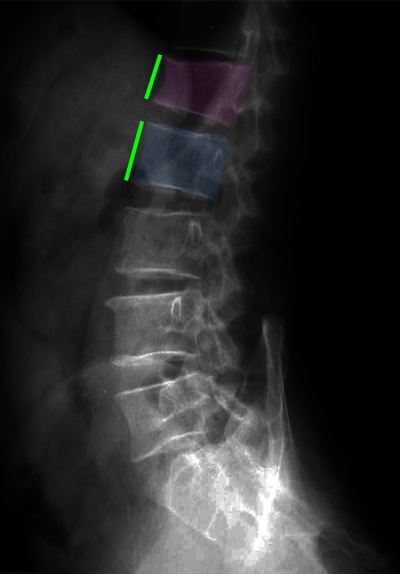

Κάταγμα 01 (φούξια) με μείωση του ύψους του σπονδύλου σε σύγκριση με τον υποκείμενο υγιή σπόνδυλο (μπλέ)(αριστερά). Κυφοπλαστική με ανάταξη του κατάγματος και επαναφορά του ύψους του σπονδύλου στο φυσιολογικό (δεξιά). |